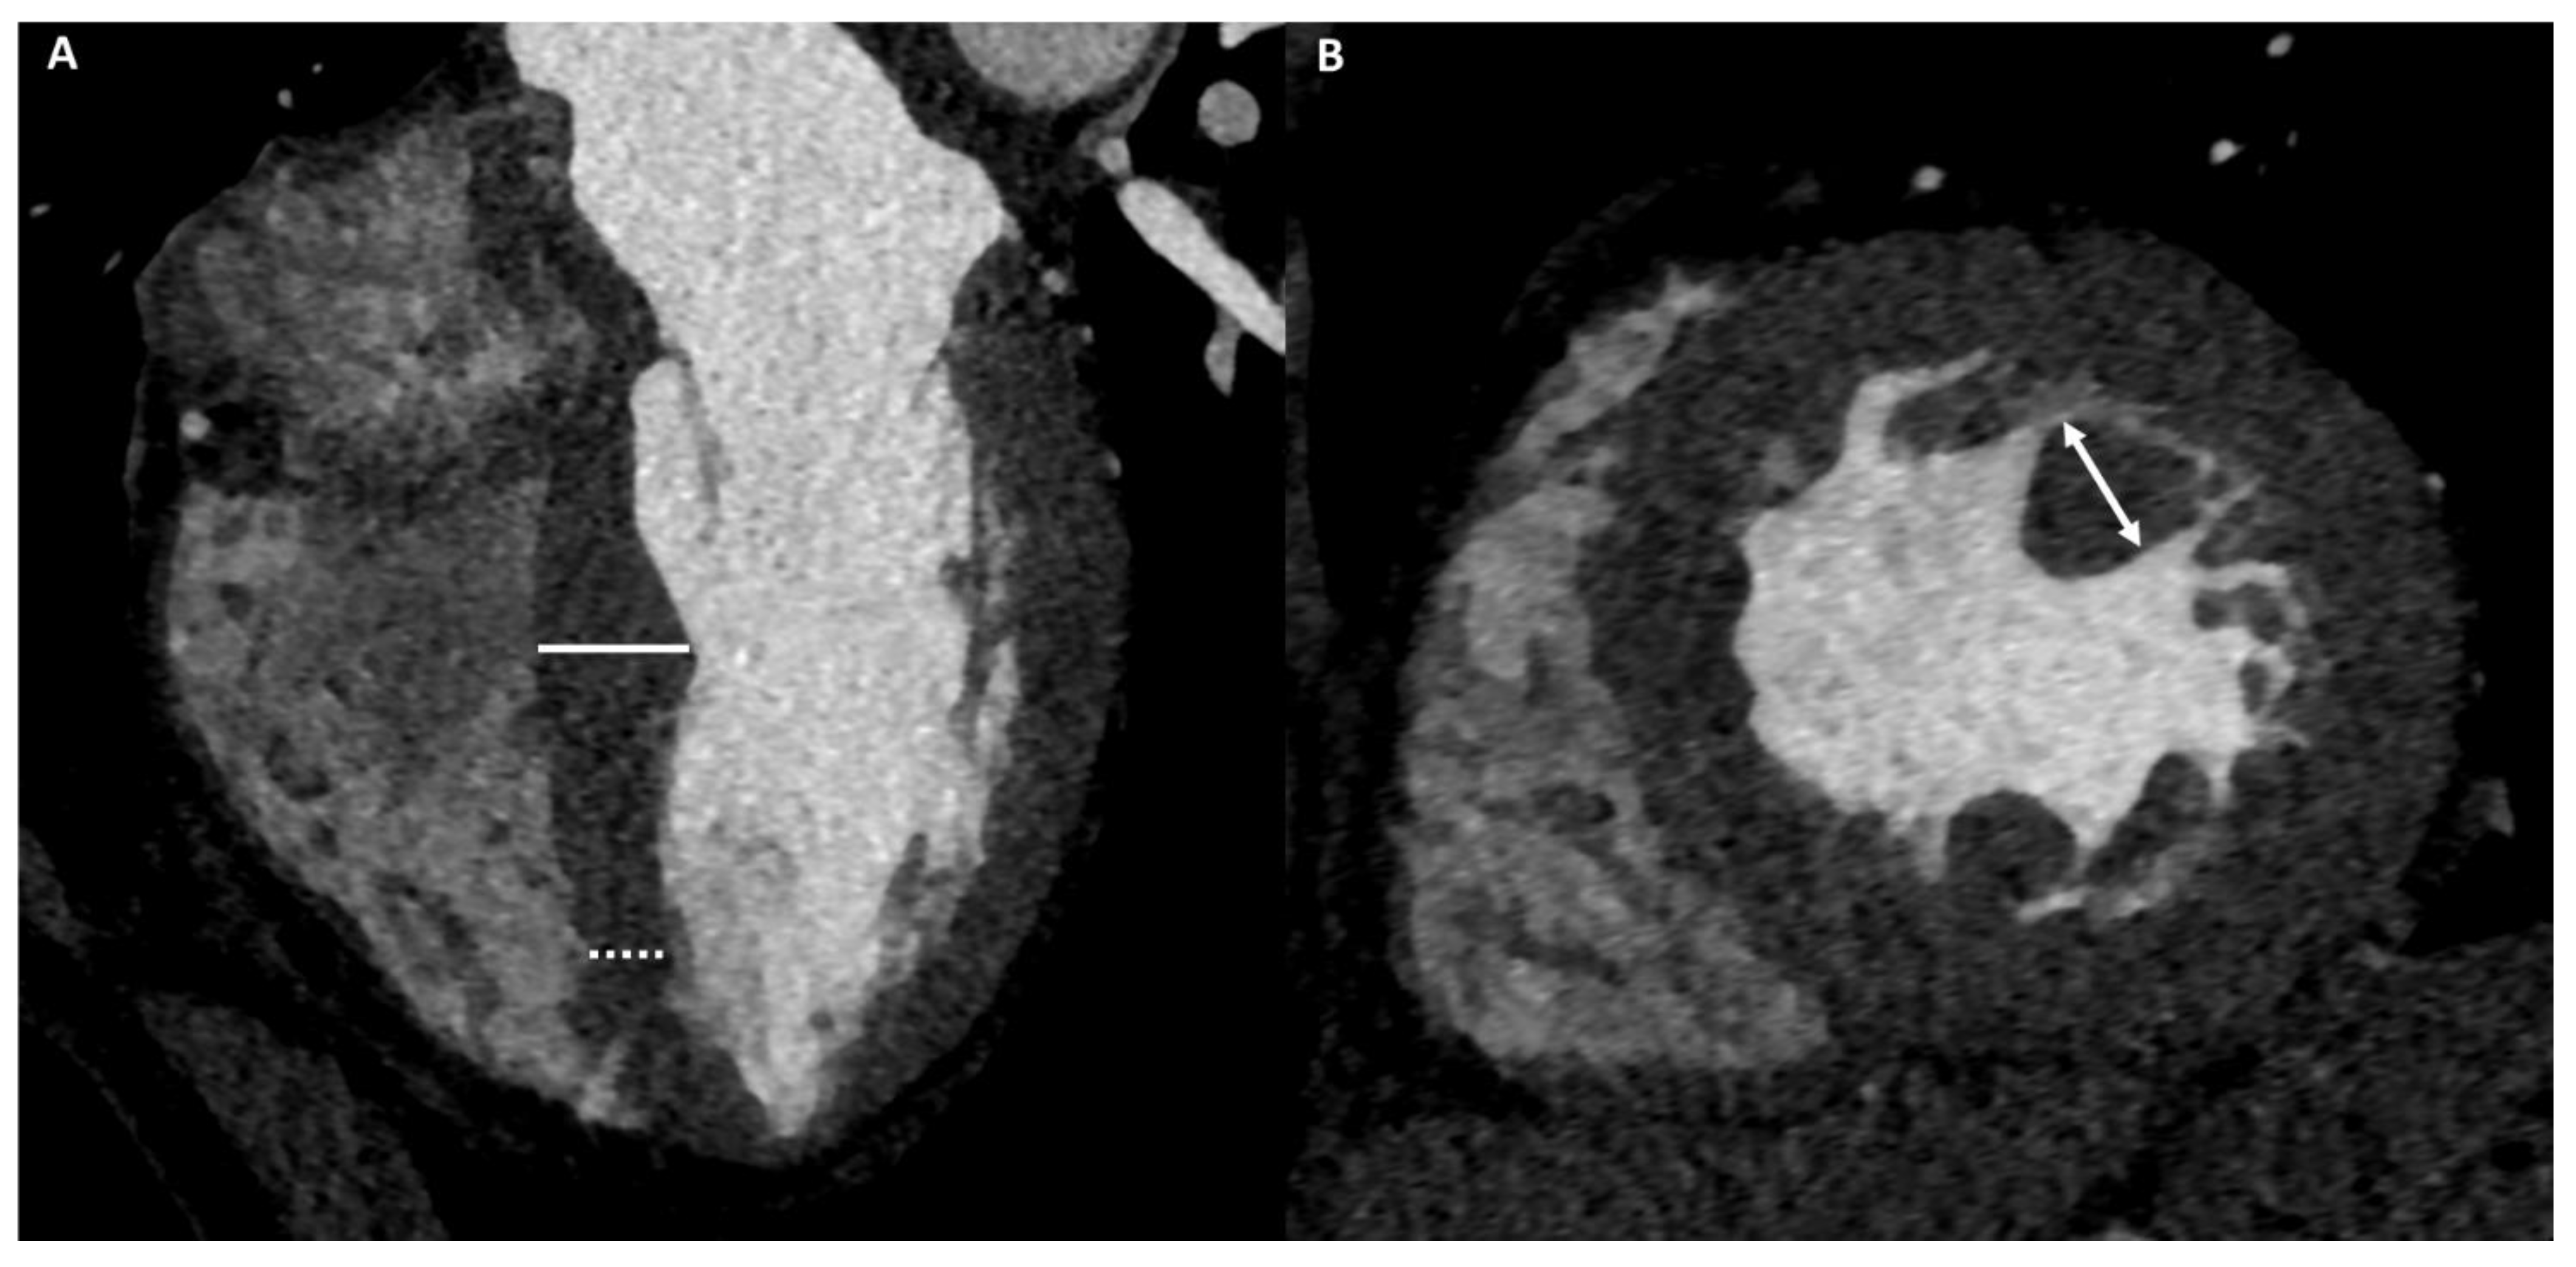

3.2. Morphological and Functional Assessment

3.3. Extracellular Volume Fraction

3.4. Late Iodine Enhancement